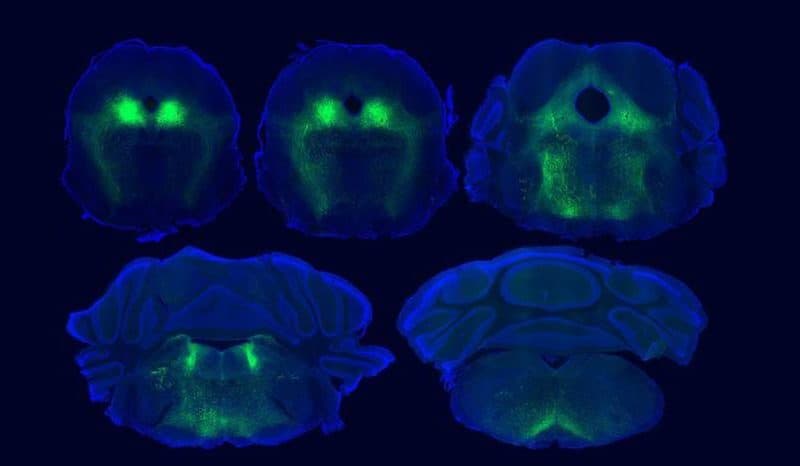

The paper is titled “Top-down control of the descending pain modulatory system drives multimodal placebo analgesia.” According to the team, theirs is the first study to establish placebo mechanisms by adapting a protocol used for humans to work in mice. Working alongside labs at the University of Pennsylvania, University of California Irvine, and elsewhere, the UCSD team detected activity in parts of the mouse brain that correspond to those previously implicated in human studies. Furthermore, by precisely mapping neural pathways and brain activity in the mice, the team identified essential roles for neural circuits that link the cortex to the brainstem and spinal cord during placebo pain relief.

Full details of the findings and methods used are provided in the paper. In it, the teams explain that they used sensor technology and a light-activated drug developed in the Banghart lab to study the role of naturally-occurring opioid peptides in the brain. Specifically, they used the sensors to detect opioid peptide signaling in the ventrolateral periaqueductal gray (vlPAG) region, a known hub for pain signaling, during placebo trials. They then used the light-activated drug called photoactivatable naloxone, or PhNX, to establish that these opioid peptides actually drive pain relief in a manner similar to drugs like morphine. The light allowed the scientists control and timing of the opioid signaling interference. Using PhNX, they confirmed that both morphine-induced pain relief and placebo pain relief use the same opioid signaling pathway in the vlPAG region of the brain.